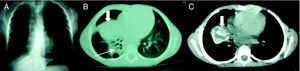

A) Rx anteroposterior de tórax: muestra una consolidación pulmonar en lóbulo medio con ensanchamiento paratraqueal derecho y una lesión enfisematosa en el hemitórax derecho. B-C) TACAR pulmonar: muestra adenopatías mediastínicas derechas (C) y una colección loculada bien delimitada de aspecto necrótico parcialmente calcificada (flechas gruesas), de gran tamaño (3,5 x 4cm), e imágenes adyacentes de consolidación pulmonar con componente atelectásico en lóbulo inferior derecho y lóbulo medio (flecha fina).

Se trata de un varón de 6 años sin antecedentes personales destacables y con historia familiar de TBC-P en abuela fallecida hacía dos años y madre y tías maternas tratadas exitosamente de TBC-P, sin sensibilidad conocida. Refería discreta pérdida de peso y anorexia en los últimos tres meses. Se realizó Mantoux que resultó positivo (20mm) y radiografía anteroposterior de tórax (fig. 1A) que mostró una consolidación pulmonar en lóbulo medio con ensanchamiento paratraqueal derecho y una lesión enfisematosa en el hemitórax derecho. La TACAR pulmonar (fig. 1B-C) objetivó adenopatías mediastínicas derechas y una colección loculada bien delimitada de aspecto necrótico parcialmente calcificado, compatible con un tuberculoma pulmonar de gran tamaño (3,5 x 4cm) e imágenes adyacentes de consolidación pulmonar con componente atelectásico en lóbulo inferior derecho y lóbulo medio y un enfisema lobar por efecto valvular endobronquial. Ante esta situación se instauró tratamiento de TBC-P con isoniazida (5mg/kg/día), rifampizina (10mg/kg/día) y pirazinamida (20mg/kg/día) y se realizó exéresis del nódulo pulmonar mediante toracotomía. El estudio anatomopatológico confirmó el diagnóstico. Tras la cirugía el paciente completó 6 meses de tratamiento antituberculoso, con evolución clínica-radiológica favorable.